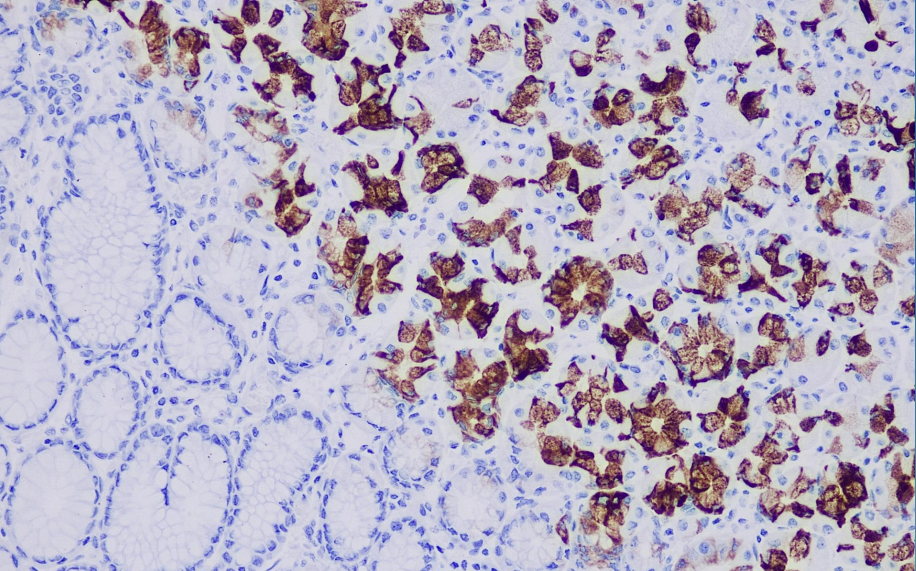

Positive control: Stomach

The Muc-6 gene, one of the mucin genes that make up the gastric mucosa, is normally expressed in the glands at the base of the gastric antrum, and its expression tends to be down-regulated in gastric pre-cancerous lesions and gastric cancer tissues.

The MUC-6 antibody reagent can specifically bind to the MUC-6 molecular antigen. The immunohistochemical kit containing the MUC-6 antibody reagent is suitable for the precise diagnosis of gastric differentiated tumors (such as gastric adenocarcinoma, pancreatic ductal adenocarcinoma and certain mucinous ovarian cancers).